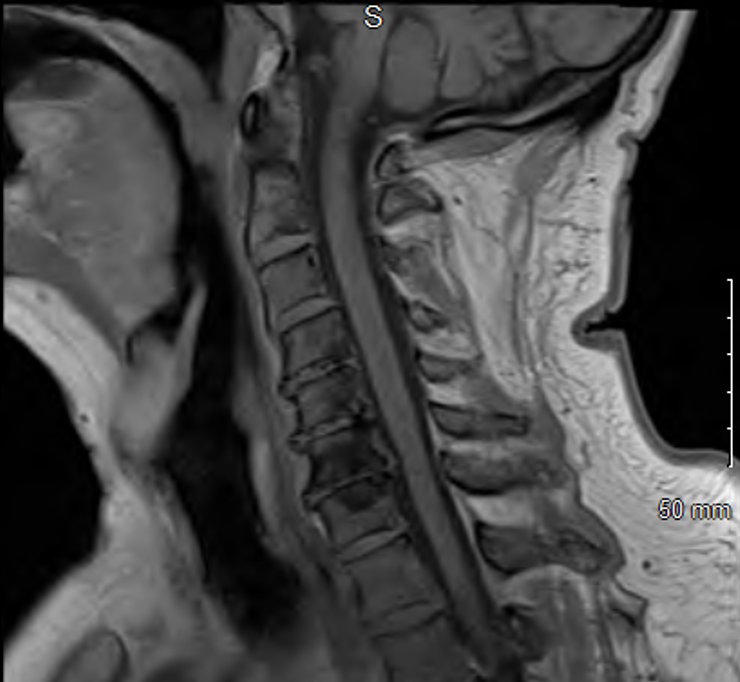

Figure 2. Brain MRI, transverse view, showing only mild chronic microvascular changes

Initial workup with CBC, CMP, ESR, CRP, viral panel, head CT, MRI of the brain and neck were unremarkable. A video and barium swallow confirmed severe dysphagia and patient was kept NPO. Differentials included Miller Fisher Variant of Guillain-Barre Syndrome (GBS) and MG.